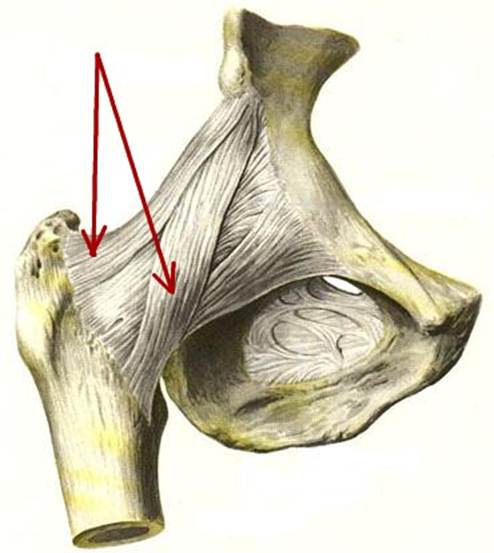

S: На рисунке обозначен art. Coxae (латинский язык).

S: Стрелки указывают на lig. iliofemorale

S: Стрелка указывает на lig. pubofemorale

S: Стрелка указывает на labrum acetabuli

S: Стрелка указывает на lig. Capitis femoris

S: Стрелка указывает на facies lunata